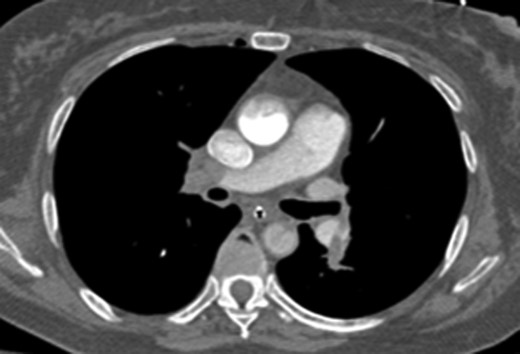

Once stable, imaging confirmed PE (Fig. 2) with a RV to left ventricle (LV) ratio of 2.1 (Fig. 3). The patient was then admitted to the ICU requiring inotropic support. Approximately 4 h later, the patient had concerning features of abdominal compartmental syndrome with increase abdominal distention and bladder pressures >25 mmHg was noted. Repeat imaging showed large volume hemoperitoneum emanating from the left hepatic lobe (Fig. 4). The patient underwent a decompressive laparotomy with a non-anatomic liver resection of segments I and II and temporary abdominal closure. Due to concerns of distal limb ischemia of the arterial cannulation site, an 8-Fr reperfusion cannula was placed in the left superficial femoral artery (SFA).

CTA chest demonstrating significant RV strain with a RV/LV ratio of 2.1.